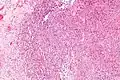

-

Intermed. mag. -

High mag. -

High mag. (SMARCB1)